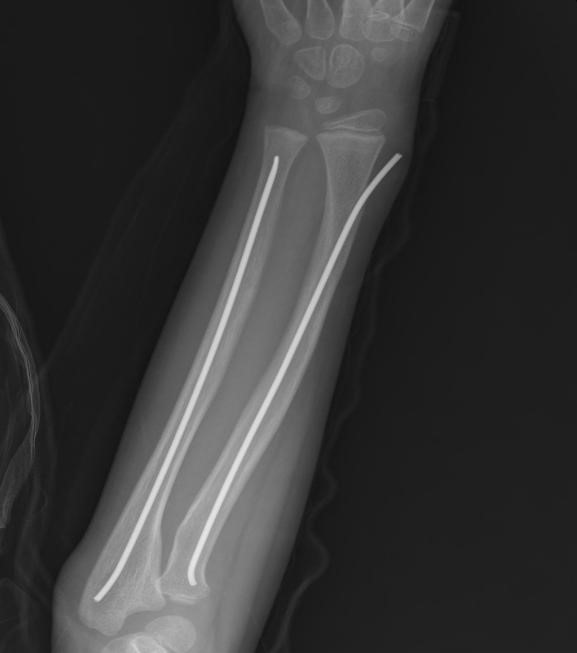

患者术后影像资料